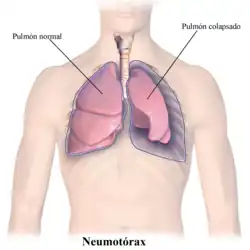

Pneumotórax (do grego, pneumo ar; thorax peitoral) é uma emergência médica causada pela presença de ar entre as membranas que envolvem os pulmões (cavidade pleural) e gera um pulmão colapsado (atelectasia) disfunção nos alvéolos, causada pelo extravasamento de líquido da pleura. Pode afetar um ou ambos pulmões e causar dificuldade para respirar (dispneia).[1]

A formação do derrame gasoso, após a ruptura pleural, eleva a pressão intrapleural e o pulmão tende ao colapso. Um pneumotórax de grandes proporções ou um pneumotórax aberto tende a aumentar progressivamente a pressão intrapleural ocasionando o colapso do pulmão, desvio do mediastino, compressão das veias, queda do débito cardíaco e hipotensão arterial.

O pneumotórax desenvolve-se quando o ar passa para a cavidade torácica que rodeia o pulmão (espaço pleural), com a possibilidade de que este possa ser comprimido. Um colapso parcial do pulmão pode não ter sintomas nem requerer tratamento algum. No entanto, quando o pulmão colapsado está muito comprimido, pode representar uma grave ameaça para a vida, particularmente numa criança com uma doença pulmonar grave. O ar preso pode colapsar fortemente o pulmão, dificultando a respiração e obstruindo a circulação do sangue dentro da cavidade torácica. Nesse caso, o ar que rodeia os pulmões deve aspirar-se rapidamente mediante uma agulha ou um tubo.